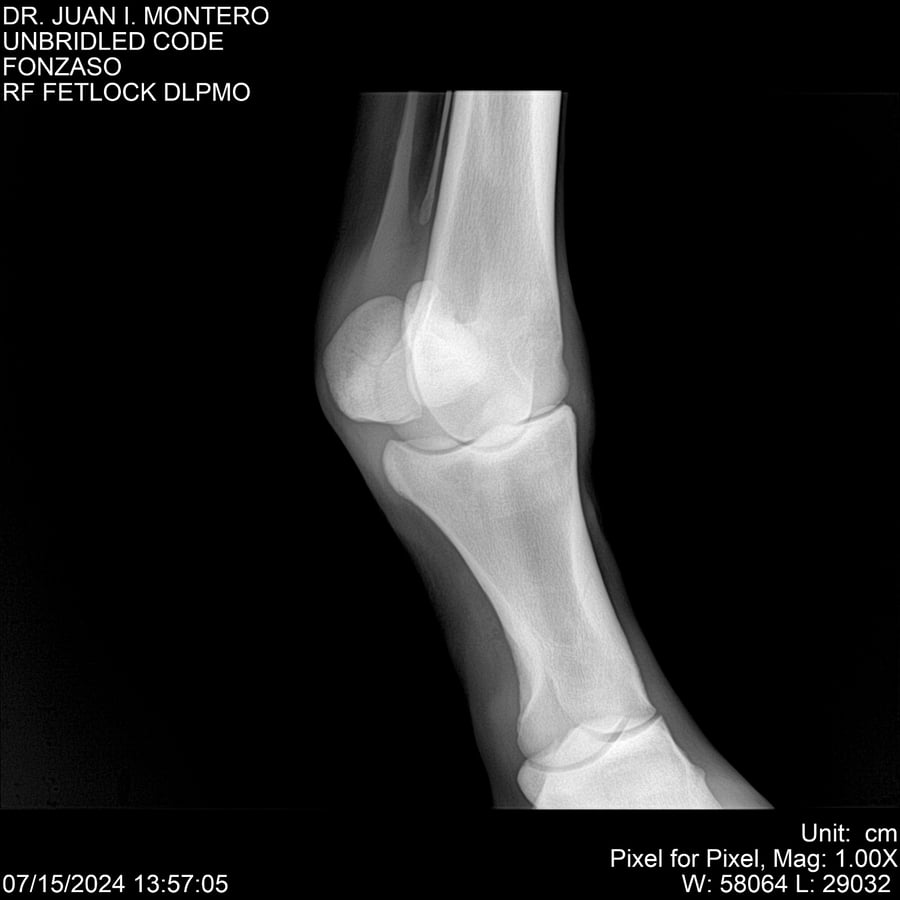

• Empresa: Abelenda N. R., Walter Hugo